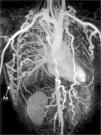

A 22-year-old man was referred to our cardiology department for investigation of hypertension. At presentation his blood pressure was 170/100 mmHg in both arms, and heart rate was 74 beats/min. The pulses were equal over both upper extremities, but bilateral femoral and popliteal pulses were extremely weak and the dorsalis pedis and anterior tibial pulses were not palpable. His past history was unremarkable except for hypertension. There was a II/VI systolic ejection murmur in the left second intercostal area and left scapular region in the back. Transthoracic echocardiography showed concentric left ventricular hypertrophy with normal ventricular function. Magnetic resonance (MR) angiography showed interruption of the descending aorta after the branching of the left subclavian artery (Figure 1). Dilated intercostal, intramammary and thoracodorsal arteries with accompanying anastomosis between the intercostal and thoracodorsal arteries were observed (Figure 2).

Three-dimensional volume rendering magnetic resonance angiography images: (A) left posterior oblique view and (B) right posterior oblique view, showing interruption of the descending aorta after the branching of the left subclavian artery. IA: interrupted aorta; IMA: internal mammary artery; LCCA: left common carotid artery; LSCA: left subclavian artery; RCCA: right common carotid artery; TrBc: truncus brachiocephalicus.